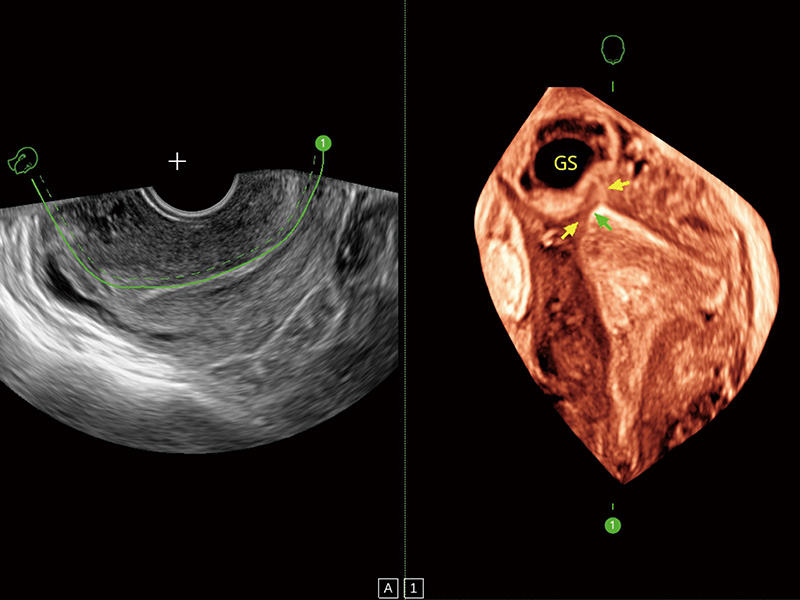

腔内容积探头

腔内三维成像技术获得显著提升,超大扇角在满足日常基础扫查的同时,支持卵泡自动测量及多种三维渲染模式,为您提供更多的诊断信息,尤其是在子宫畸形的诊断,内膜及肿瘤占位观测中起到了重要的作用。